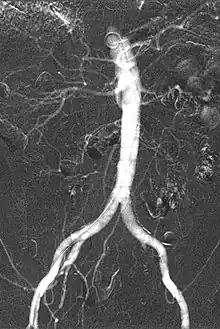

CO2 Angiogram showing Abdominal Aorta, visceral arteries and iliac arteries

Carbon dioxide angiography is a diagnostic radiographic technique in which a carbon dioxide (CO2) based contrast medium is used - unlike traditional angiography where the contrast medium normally used is iodine based – to see and study the body vessels.[1] Since CO2 is a non-radio-opaque contrast medium, angiographic procedures need to be performed in digital subtraction angiography (DSA).